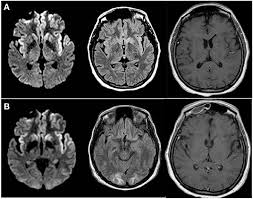

2021年には、ファイザーの遺伝子ワクチン2回目接種の1週間後に急に歩行困難、記憶障害、不穏・行動異常、頭痛を発症して亡くなった64歳の女性の症例報告がありました(Sporadic Creutzfeldt-Jakob Disease After Receiving the Second Dose of Pfiz Dose of Pfizer-BioN er-BioNTech COVID-19 V VID-19 Vaccine. HCA Healthcare 2021)。解剖の結果、クロイツフェルト・ヤコブ病(CJD)と診断されています。

遺伝子ワクチンとクロイツフェルト・ヤコブ病(CJD)などのプリオン病との関連は、拙著『ハチミツ自然治療の最前線』でエビデンスをご紹介しましたが、その後もワクチン接種後の発症報告がなされています(Creutzfeldt-Jakob Disease After the COVID-19 Vaccination. Turk J Intensive Care DOI:10.4274/tybd.galenos.2021.91885)。

モンタニエ博士たちが主張しているのは、人工ウイルスや遺伝子ワクチンのスパイクタンパク質の遺伝子の中に、プリオンの遺伝子が挿入されて設計されているということです(Towards the emergence of a new form of the neurodegenerative Creutzfeldt-Jakob disease: Twenty six cases of CJD declared a few days after a COVID-19 “vaccine” Jab. May 2022. DOI:10.13140/RG.2.2.14427.03366)。

しかし、わざわざプリオン(遺伝子ワクチンに含まれる)を外から注入あるいは、体内で産生しなくても、遺伝子ワクチンによる脳の炎症で脳内に異常タンパク質(アミロイド、異常プリオンと呼んでいるもの)が集積し、自動的に増えていくことでクロイツフェルト・ヤコブ病(CJD)のようなプリオン病が成立します(詳しい機序は、拙著『慢性病の原因はメタボリック・スイッチにあった!』)。

フランスでは、1992~2019年までの27年間で、クロイツフェルト・ヤコブ病(CJD)の発症例は、わずか28症例でした。しかし、2019年の遺伝子ワクチン接種開始以降は、一年間ですでに26症例にのぼっています。

もちろん、遺伝子ワクチン接種後の有害事象は過少申告ですから、遺伝子ワクチンによるクロイツフェルト・ヤコブ病(CJD)の発症は30倍以上になっているでしょう。

この極めて稀な脳の病気の急増の原因を数字は雄弁に物語っています(^_−)−☆。